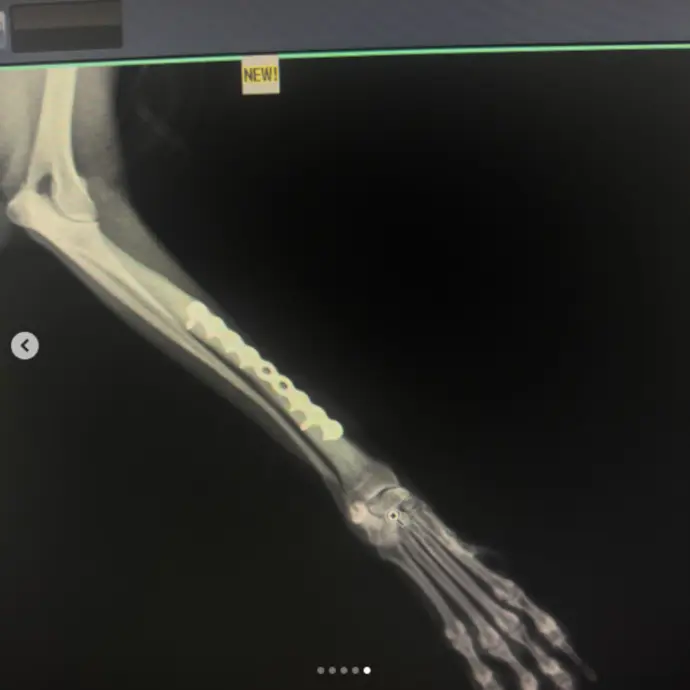

Köpeklerde Diz Kapağı Çıkığı, Çapraz Bağ Kopuğu, Kalça Çıkığı ve Kırık Ameliyatı

Uzmanlık alanları arasında bacak ve kol kırıkları, travma sonucu kalça kırıkları, yüksekten düşme sonucu oluşan travmalar, kranial ve ön çapraz bağ kopmaları, parçalı pelvis kırıkları, eklemden kırıklar, kalça çıkıkları, distal radius ve ulna kırıkları ile doğumsal kalça problemleri gibi birçok ortopedik vaka yer almaktadır.